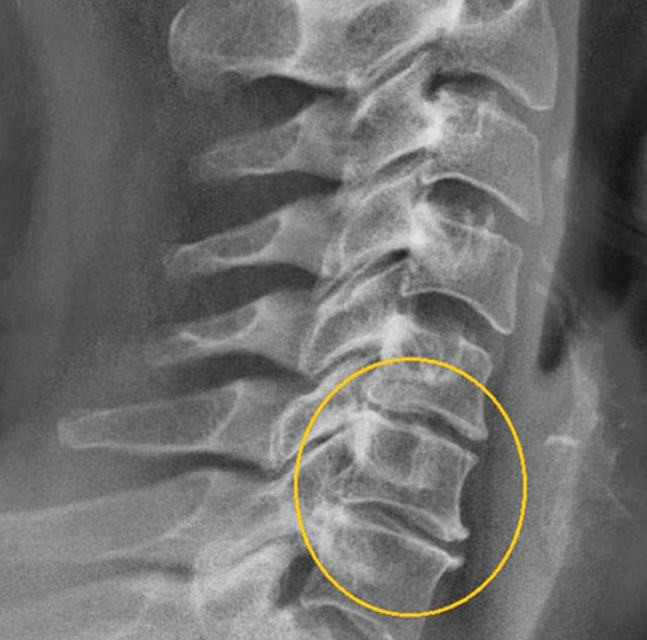

- X -Ray (jellegzetes diagnosztikai tulajdonságok a gerinc szélén lévő tüskék formájában, vagy az MPD magasságának csökkenése 2 szakaszban jelenik meg).

- CT, a gerinc MRI (lehetővé teszi az MPD változásainak diagnosztizálását a kezdeti szakaszokban).